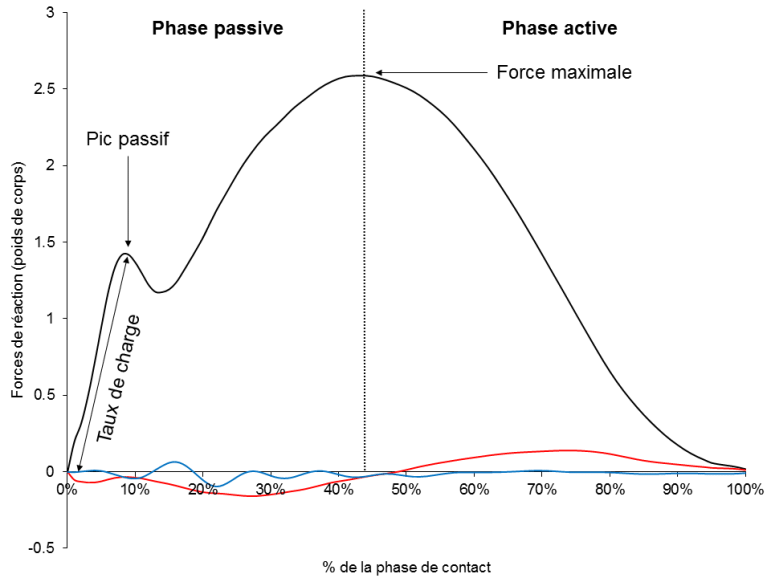

Avec l’allongement des distances, le temps requis pour retrouver une efficacité neuromusculaire et élastique est plus long. Durant cette phase que ce soit à l’entraînement ou durant une course, les membres inférieurs sont incapables de dissiper les contraintes sur l’appareil locomoteur et peuvent favoriser la transmission du stress sur la région lombaire et les genoux.

Les changements du type de contraction, de concentrique à excentrique, et du type de chaîne, de fermée et semi-portée en cyclisme à ouverte et soumise à la pesanteur en course à pied font de la transition vélo-course à pied une phase délicate.Le risque de blessures apparaît d’ailleurs statistiquement durant les premiers kilomètres de la course à pied.

Le bord postérieur de la bandelette du fascia lata affecte l’épicondyle latéral juste après que le pied ne touche le sol, moment où la jambe absorbe la force de réaction au sol.